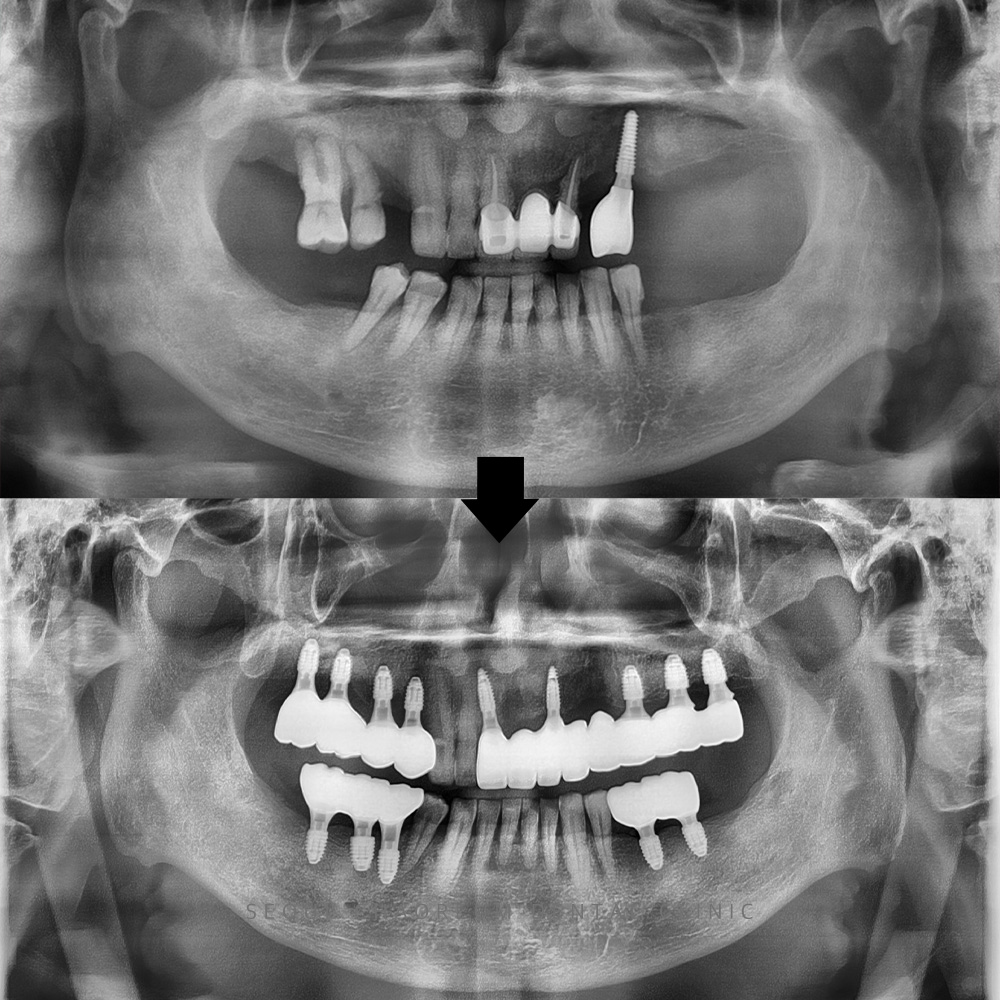

병점임플란트, 임플란트 받았던 곳이 문제가 생기고 위 앞니 보철 흔들려요 치아는 서로 균형을 이루며 기능하기 때문에, 특정 부위에 문제가 발생하면 인접 치아까지 영향을 받는 경우가 많습니다. 특히 어금니와…